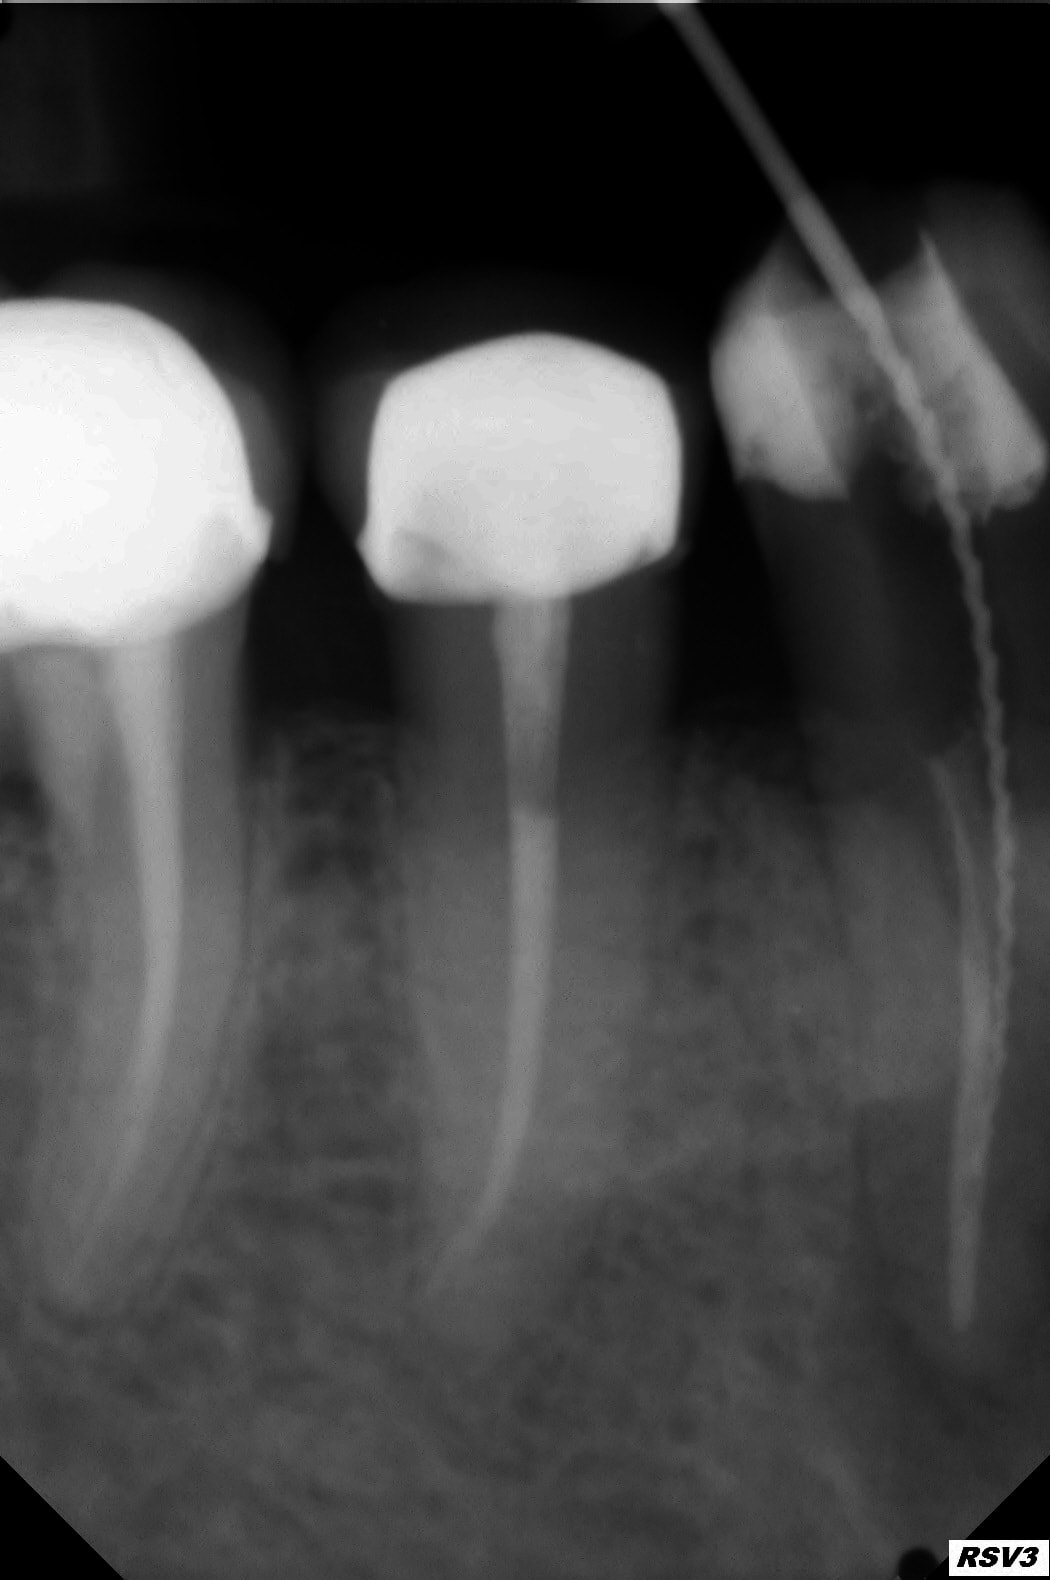

Exemple perfo magistrale en 2009, et radio 2013 et 2017 (on ne vois que la racine mésiale mais la furcation tient le coup.

46 2009 2 fujwq5 - Eugenol

46 2017 ra1wjf - Eugenol

46 2013 rwugpl - Eugenol

46 2009 cxmhe5 - Eugenol

Merci pour les photos.cela ressemble à ce qui s'est passé pour moi.j'ouvre tes la chambre avec une fraise endormi z donc je n'avais jamais eu de soucis de perfo sur une ouverture de chambre.